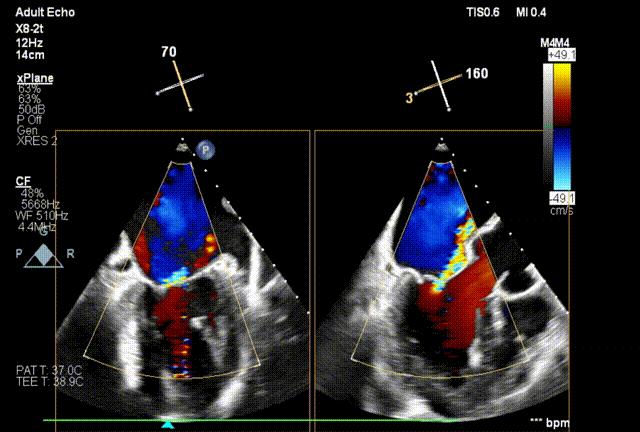

术前经食道超声(TEE)评估

术前TEE

DMR P2脱垂连枷(脱垂范围:12mm,连枷间距:3mm),反流2区,MR重度(VC:4* 10mm),A2:21mm,P2:10mm,AP:30mm,MVA约 4.7 cm²。

术后Xplane彩色图像

夹合后二尖瓣反流量0+,平均跨瓣压差3mmHg